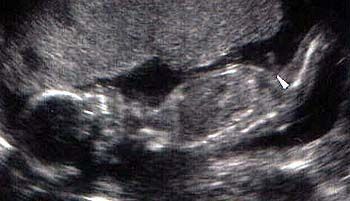

عکس جنین پسر در سونوگرافی هفته نوزدهم بارداری

همانطور که در شکل با نشانک مشخص شده است، در هفته نوزدهم بارداری آلت تناسلی بین پاها معلوم است. فرزند شما حالا نزدیک به 240 گرم وزن دارد و قدش به 15.3 رسیده است. او حالا اندازه یک انبه است.